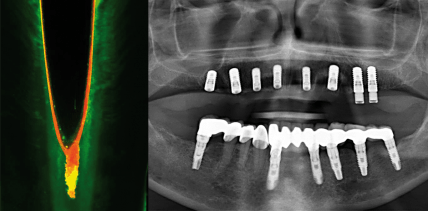

Endodontie vs. Implantologie

Durch die Einführung von Implantaten in die Zahnmedizin hat sich eine neue Diskussion ergeben, die zwei zahnmedizinische Bereiche einander gegenüberstellt: Endodontie und Implantologie. Im Folgenden sollen Hilfestellungen gegeben werden, um die damit verbundenen Probleme lösen zu können. weiterlesen